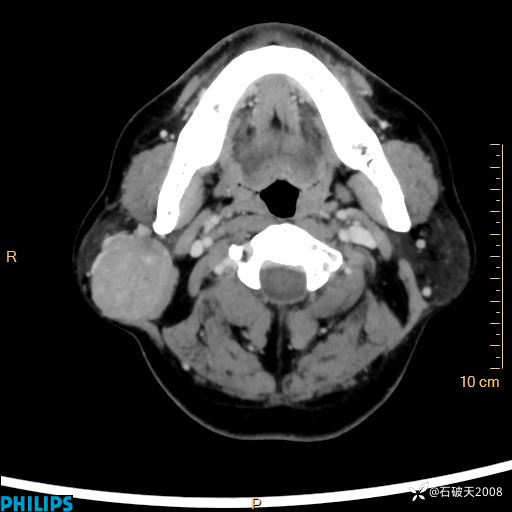

病例分享:颈部占位,一周后公布病理

男 57岁 主 诉:发现右侧颌下肿物1月余。

现病史:1月余前家属发现右侧颌下肿物。局部皮肤无红肿、热痛,无吞咽困难,无异物感,无恶心、呕吐,无头痛、头晕,无胸闷、胸痛,无发热、咳嗽、咳痰及呼吸困难。于我院行体表肿块彩超检查(2024.03.15我院)示:右侧耳下皮下软组织内低回声,未治疗。今为进一步治疗门诊以“腮腺肿瘤”为诊断收住我科,发病来患者神志清,精神可,饮食、睡眠及大小便正常,体重无明显下降。

动脉期